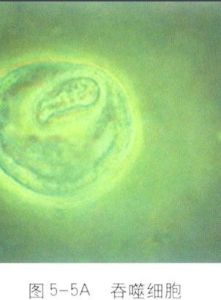

吞噬細胞以病原菌為例,吞噬、殺菌過程分為三個階段,即吞噬細胞和病菌接觸、吞入病菌、殺死和破壞病原菌。吞噬細胞內含有溶酶體,其中的溶菌酶、髓過氧化物酶、乳鐵蛋白、防禦素、活性氧物質、活性氮物質等能殺死病菌,而蛋白酶、多糖酶、核酸酶、脂酶等則可將菌體降解。最後不能消化的菌體殘渣,將被排到吞噬細胞外。

細菌被吞噬在吞噬細胞內形成吞噬體;溶酶體與吞噬體融合成吞噬溶酶體;溶酶體中多種殺菌物質和水解酶將細菌殺死並消化;菌體殘渣被排出細胞外。